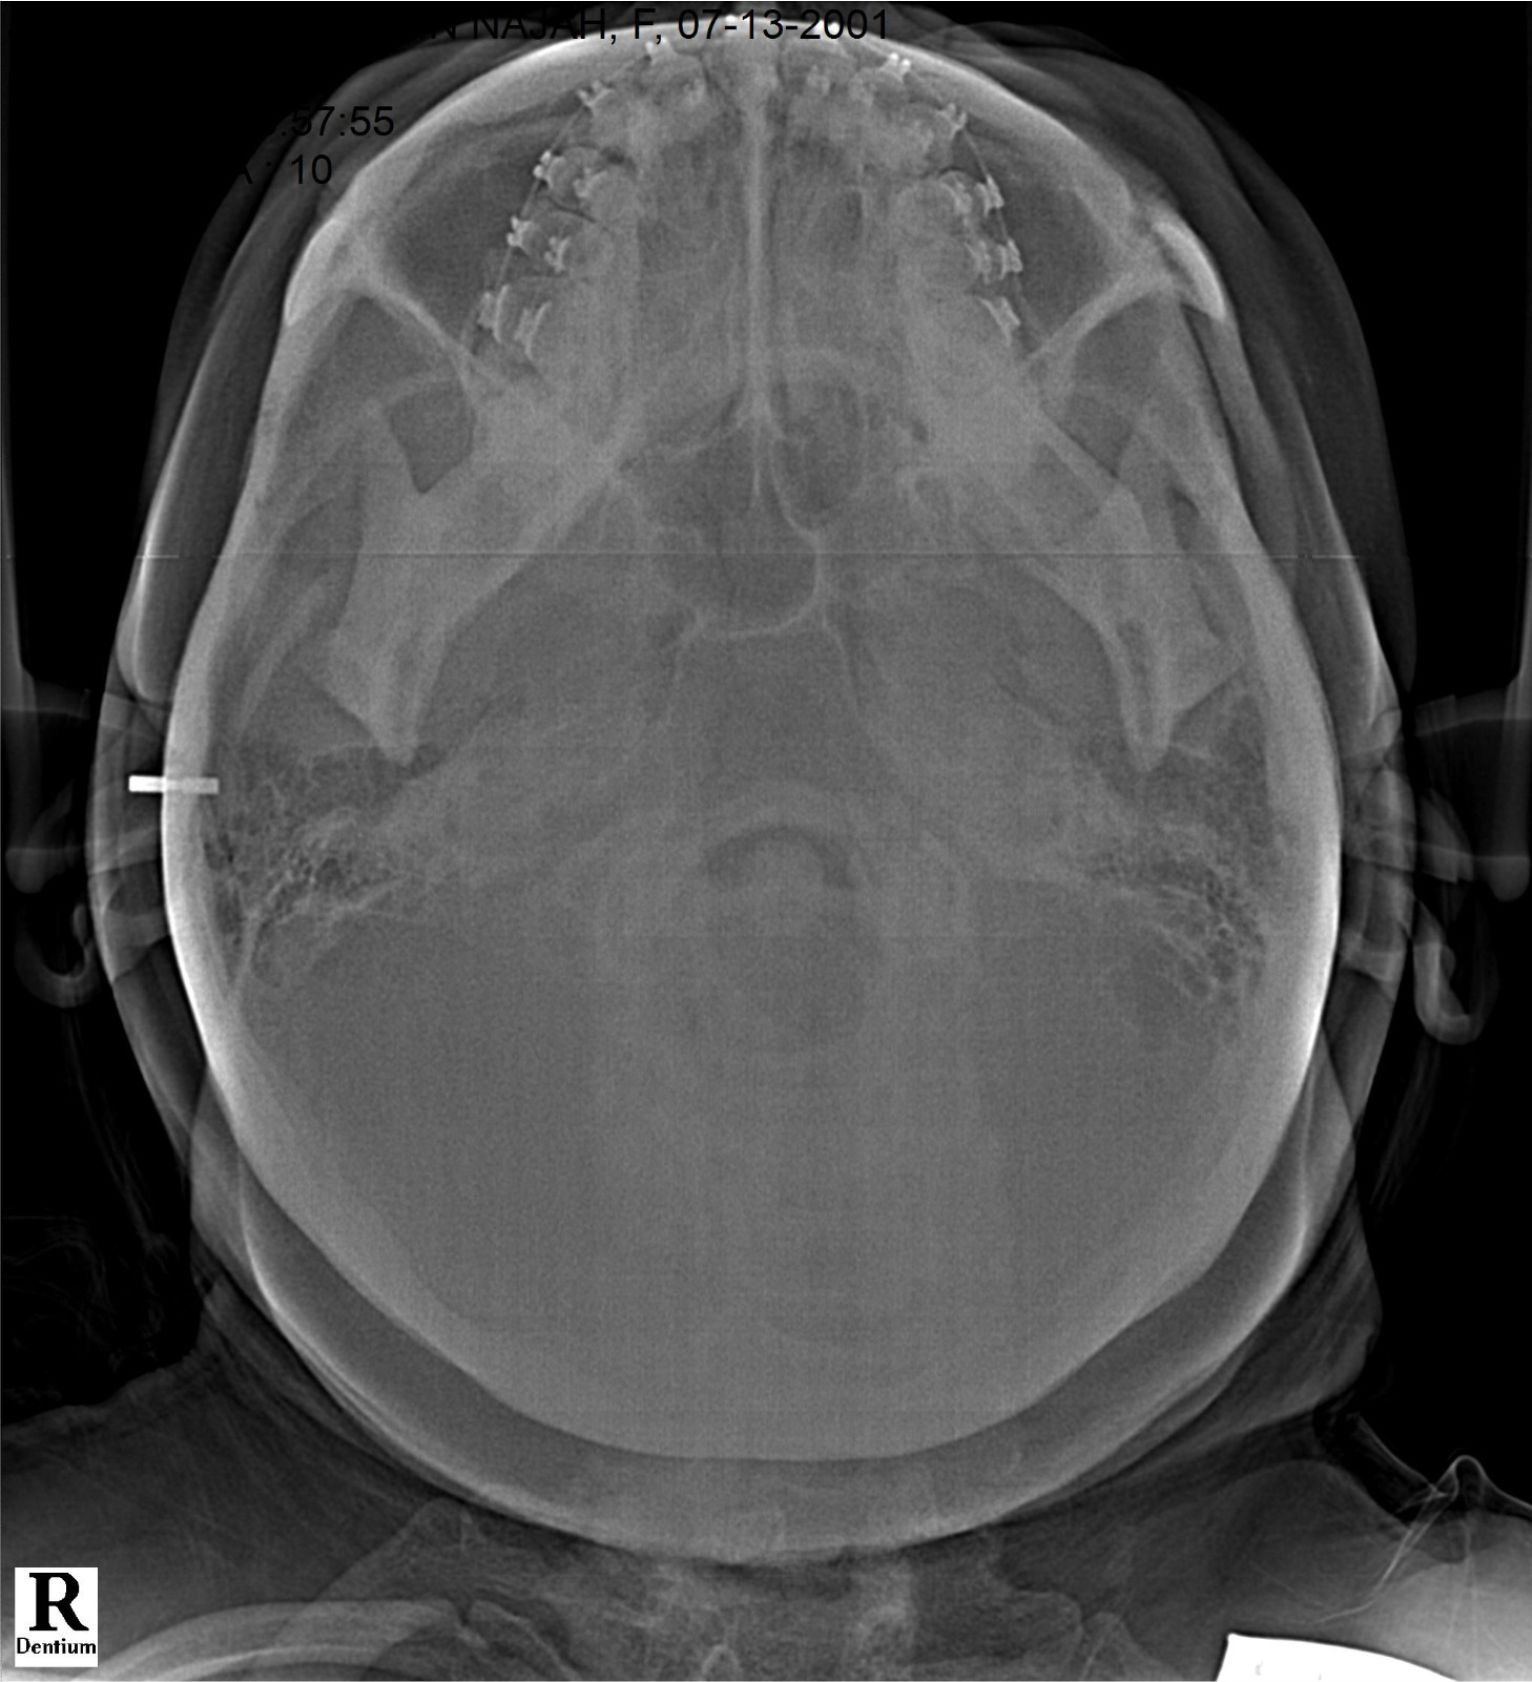

Rontgen Occipitomentale (sinus) biasa digunakan untuk kasus patah tulang diwajah hingga kasus infeksi seperti sinusitis akut.